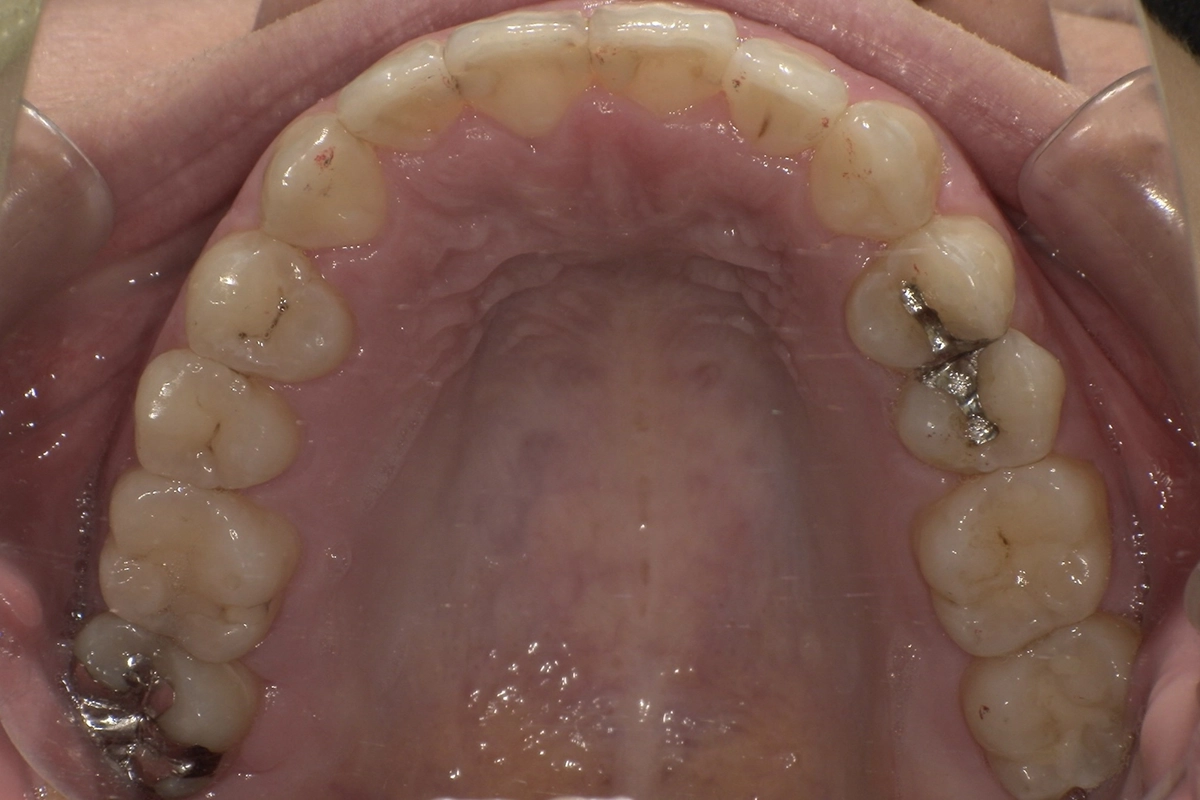

after

前方に飛び出していた歯が歯列の中に収まり、滑らかなアーチを描くようになりました。

お口の健康面

歯並びが整ったことで歯ブラシが隅々まで届きやすくなり、虫歯や歯周病の予防がしやすくなりました。